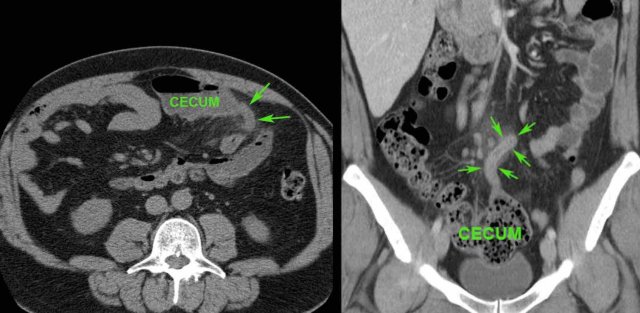

In this 16 year old patient with RLQ pain, enlarged mesenteric lymph nodes surrounded by some inflamed fat (*) were the only US finding and the appendix could not be identified.

CT confirmed the enlarged nodes (arrowheads), but revealed an inflamed appendix (arrow), originating from the cecum in deep pelvic position.

Young patients with acute appendicitis often have secondarily enlarged mesenteric lymph nodes.